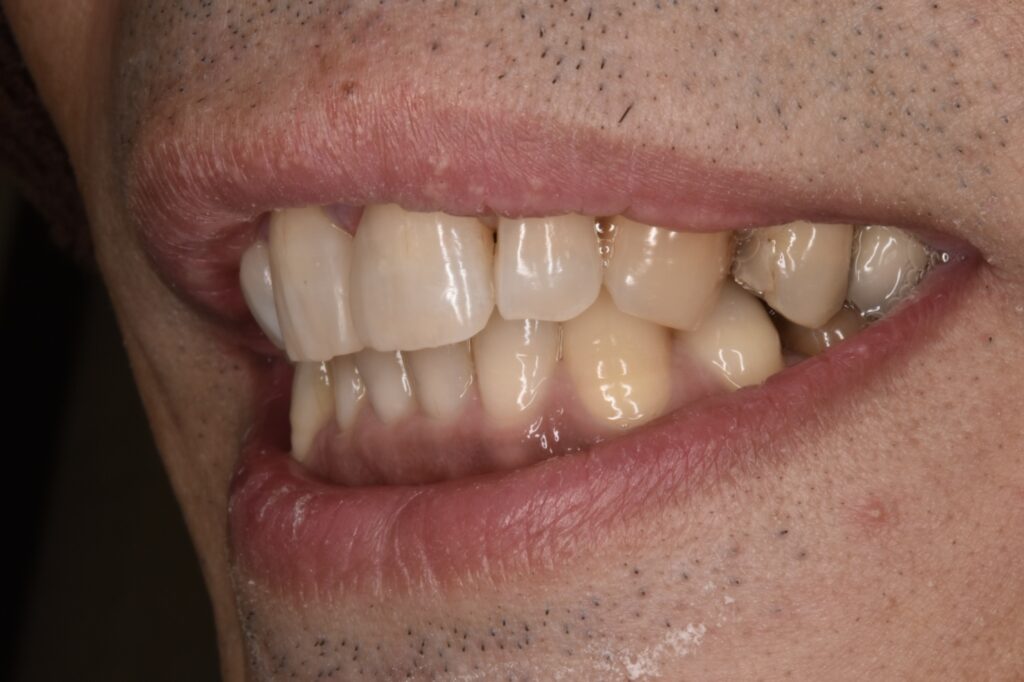

治療後

約2時間後です。

治療前とは比べ物にならないほど自然だと大変喜んでくだいました。歯のもっこり感もなくちゃんとフロスも通ります。